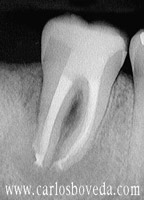

Video de un Retratamiento de Conductos en Una Sesión - (formato Quicktime)